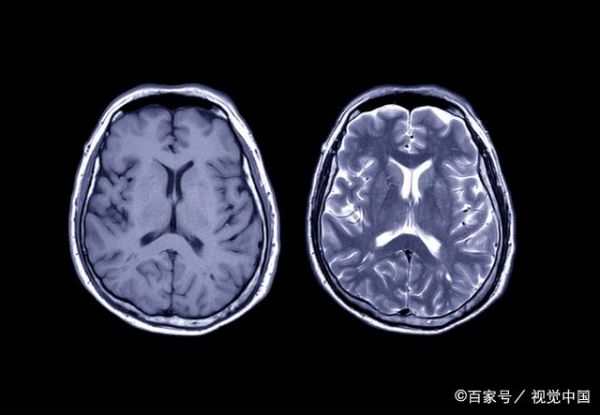

脑卒中是一种紧急情况,需要迅速而有效的医疗干预。当患者被送入急诊室时,急救医生会立即进行初步评估,包括检查症状、评估生命体征和进行神经检查。随后,医生通常会使用神经影像学技术,以确定脑卒中的类型和严重程度。这有助于医生确定是否为缺血性脑卒中(由血栓或栓子引起)或出血性脑卒中(由出血引起),因为治疗方法可能有所不同。